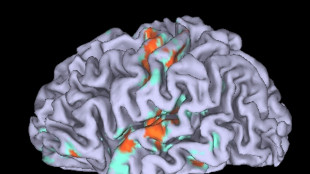

Cervello, la dopamina può alterare il senso di controllo e le decisioni

Studio italiano sui malati di Parkinson

Un chip nel cervello aiuta i malati di Parkinson a camminare

Positivi i risultati di un test su 40 persone